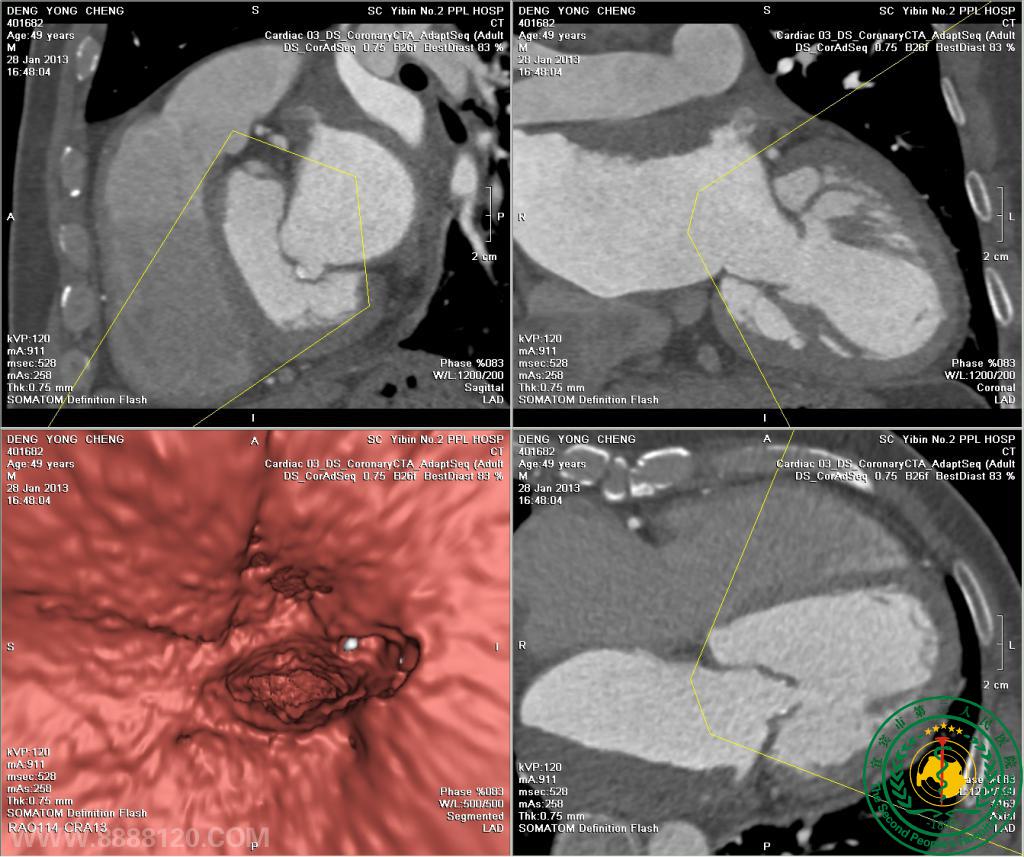

应用举例一 风心病术前检查(如下图):

左心房室明显扩大,舒张期左心房短径6.1cm,左心室短径6.1cm,左心房室后上部大块不规则形充盈缺损,大小约2.3cm×5.3cm×3.6cm,无强化,右后缘局部斑片状钙化。右心房室略扩大。心脏各房室壁未见确切异常密度影。

二尖瓣明显钙化,以下部为主,舒张期开口大小约13mm×7mm,收舒期未完全闭合。主动脉瓣后部明显增厚、钙化,收缩期开口不全。扫及双侧肺血管和主动脉未见异常。

左右冠状动脉起源于左右冠状动脉窦内上部,分布走行未见异常,呈右冠优势型。左右冠状动脉各段壁光整,表面无心肌覆盖,腔连续通畅。

诊断意见:

1.左心房室明显扩大,右心房室略扩大,二尖瓣钙化伴狭窄和关闭不全,主动脉瓣钙化伴狭窄,考虑为风心病。

2.左心房后上部充盈缺损(多为附壁血栓),右后缘斑片状钙化。

3.左、右冠状动脉未见异常。